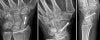

X-ray : 주상골 골절(Scaphoid fracture)

초기에는 X-ray 검사(AP/Lat/Scaphoid(Billiard view)이 기본)에서 나타나지 않을 수 있으므로 임상적으로 의심되는 환자는 초기 X-ray 검사를 척골 치우침 자세로 촬영합니다.

여기에서도 정상이면서 통증이 2~3주간 지속되면 반복해서 X-ray 검사를 하고(>10% of cases : Repeat imaging in 2 weeks will often show fracture) MRI 검사를 합니다.